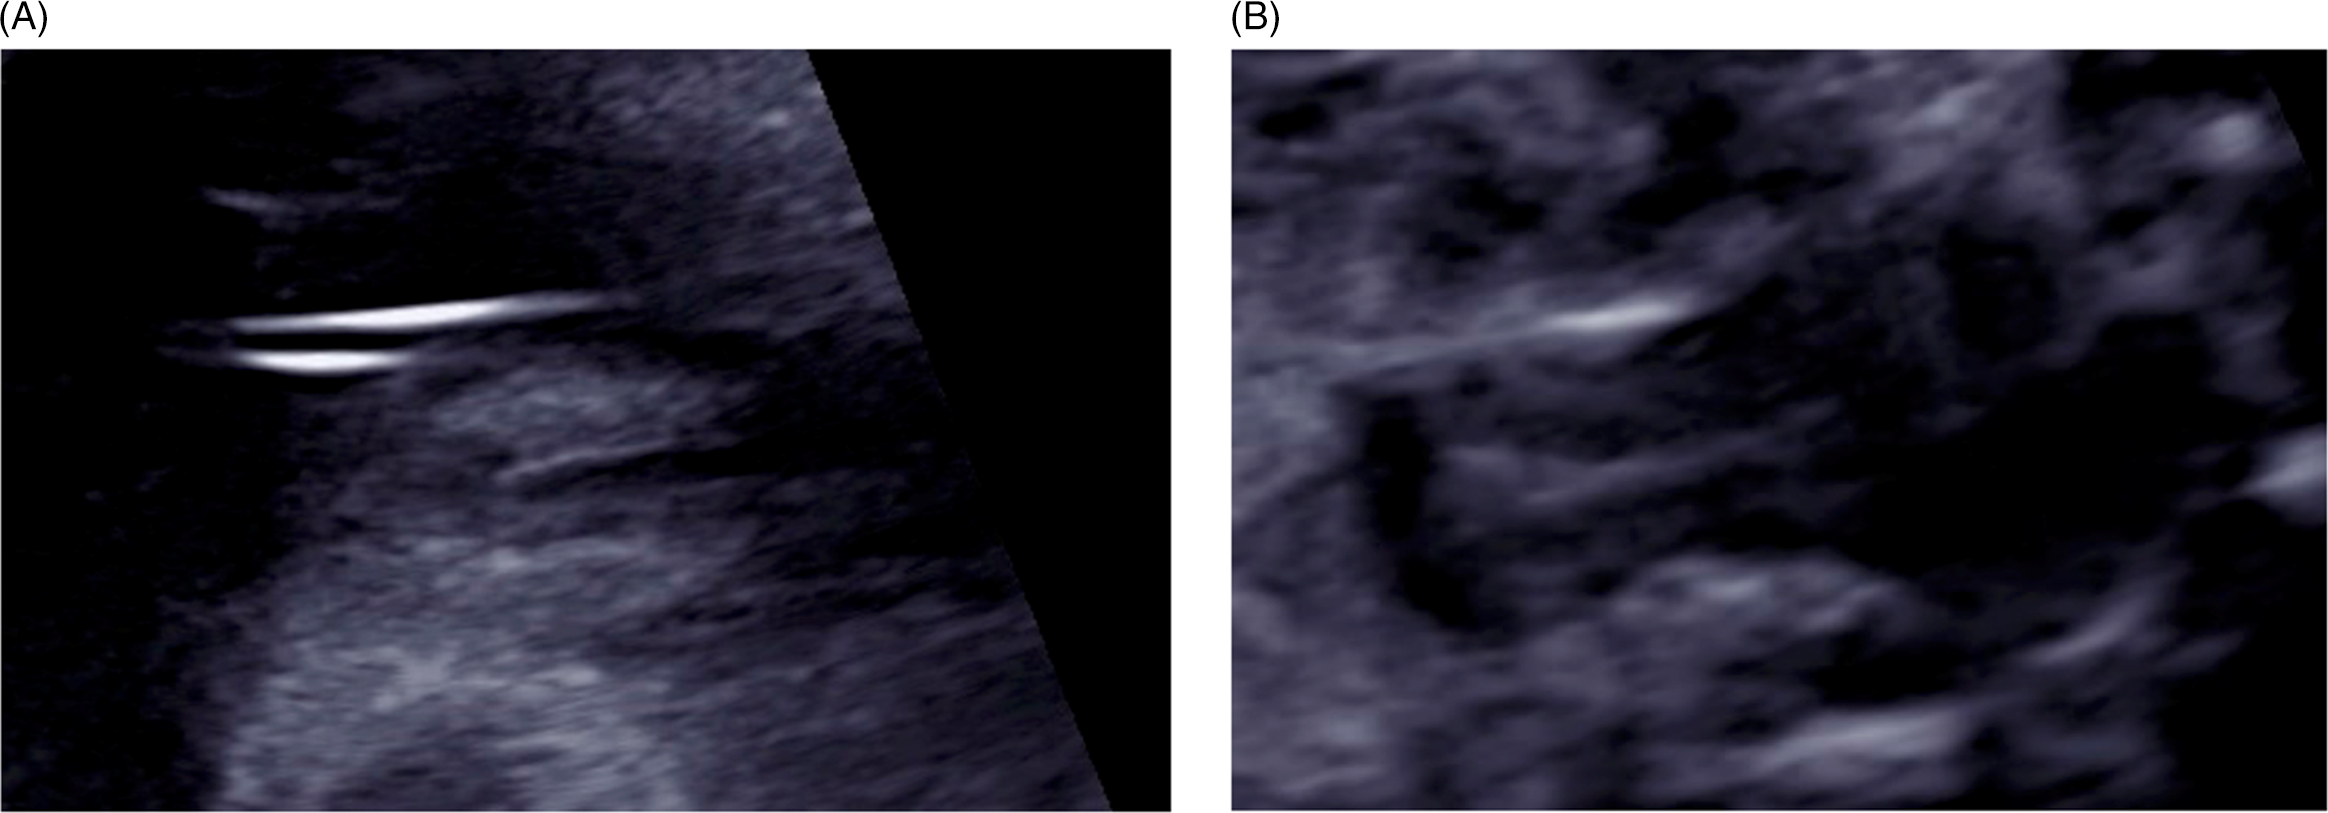

A 30-year-old primipara who conceived spontaneously was diagnosed with a monochorionic (MC) diamniotic twin pregnancy through ultrasonographic findings at 9 weeks’ gestation because there were two fetuses. They were in a common gestational sac, and each had its own amniotic cavity. The primipara was referred to us at 12 weeks’ gestation for the management of her twin pregnancy. At 26 weeks, serial scans showed that the fetuses had a different sex. No abnormalities were found in their anatomy, including the genital organs. The twins were delivered via cesarean section at 38 weeks’ gestation. Apgar scores and pH values were normal. Twin A was a phenotypically normal female, with a birth weight of 2612 g, and Twin B was a phenotypically normal male, weighing 2458 g. Histological examination of the placenta confirmed MC diamniotic twinning (see Figures 1 and 2). Karyotyping was performed on each umbilical cord blood and revealed the chimeric karyotypes 46,XX[15]/46,XY[15] and 46,XY[21]/46,XX[9] for Twin A and Twin B, respectively. Ultrasonography determined normal female and male internal genitalia concordant with their phenotypes (see Figures 3 and 4). Karyotyping was performed again from blood samples at 7 months of age. The results confirmed that the twins had similar chimericg karyotypes: 46,XY[7]/46,XX[13] in Twin A and 46,XX[9]/46,XY[11] in Twin B.

Fig. 2. Monochorionic–diamniotic twin pregnancy in the ninth gestational week.